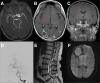

Results: We identified 12 cases of cerebral pseudoprogression in 123 patients treated with ICIs and sufficient MRI. These patients were receiving ICI therapy for lung cancer (n=5), malignant melanoma (n=4), glioblastoma (n=1), hepatocellular carcinoma (n=1) or lymphoma (n=1) when cerebral pseudoprogression was detected. Median time from the start of ICI treatment to pseudoprogression was 5 months. All but one patient developed neurological symptoms. Three different patterns of cerebral pseudoprogression could be distinguished: new or increasing contrast-enhancing lesions, new or increasing T2 predominant lesions and cerebral vasculitis type pattern.

Conclusion: Cerebral pseudoprogression followed three distinct patterns and was detectable in 3.2% of all patients during ICI treatment and in 9.75% of the patients with sufficient brain imaging follow up. The fact that all but one of the affected patients developed neurological symptoms, which would be classified as progressive disease according to iRANO criteria, mandates vigilance in the diagnosis and treatment of ICI-induced cerebral lesions.